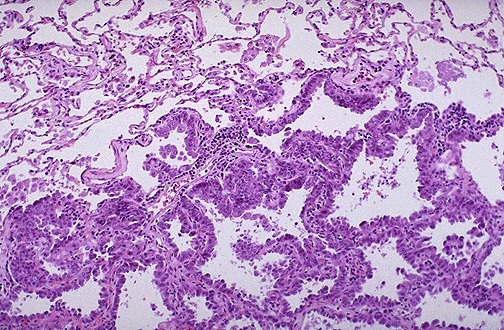

![]() | Microscopically, the bronchioloalveolar carcinoma is composed of columnar cells that proliferate along the framework of alveolar septae. The neoplastic cells are well-differentiated. These neoplasms, a form of adenocarcinoma, in general have a better prognosis than most other primary lung cancers, but they may not be detected at a low stage. |